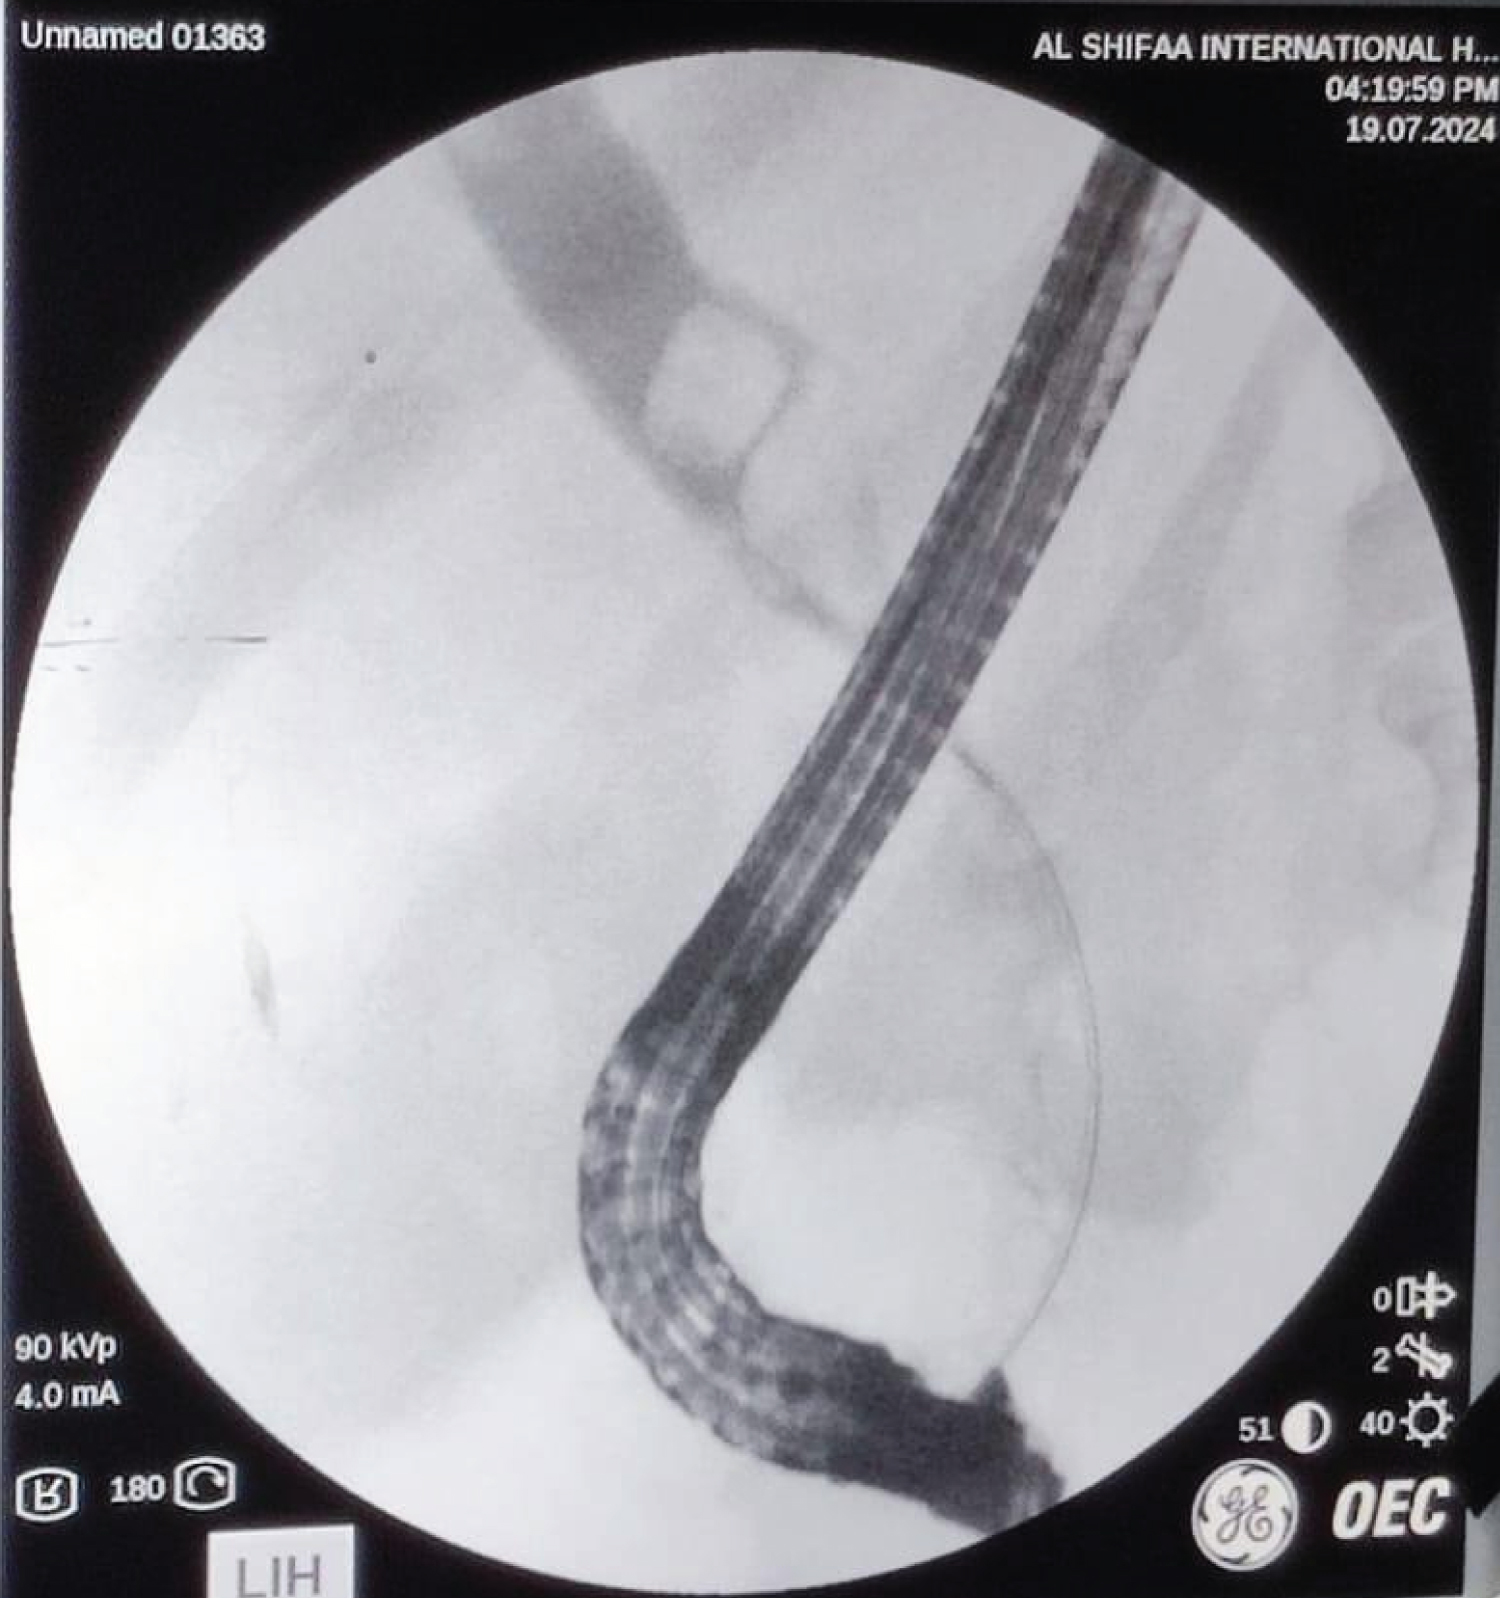

All procedures were performed by experienced endoscopists (> 500 ERCPs) or surgeons (> 50 CBDEs) (Photomicrograph 1, Photomicrograph 2 and Photomicrograph 3).

Photomicrograph 2: Showed the hologram of the endoscopic technique of ERCP to remove the CBD stone. View Photomicrograph 2

Photomicrograph 3: Showed open surgical exploration to remove the CBD stone. View Photomicrograph 3